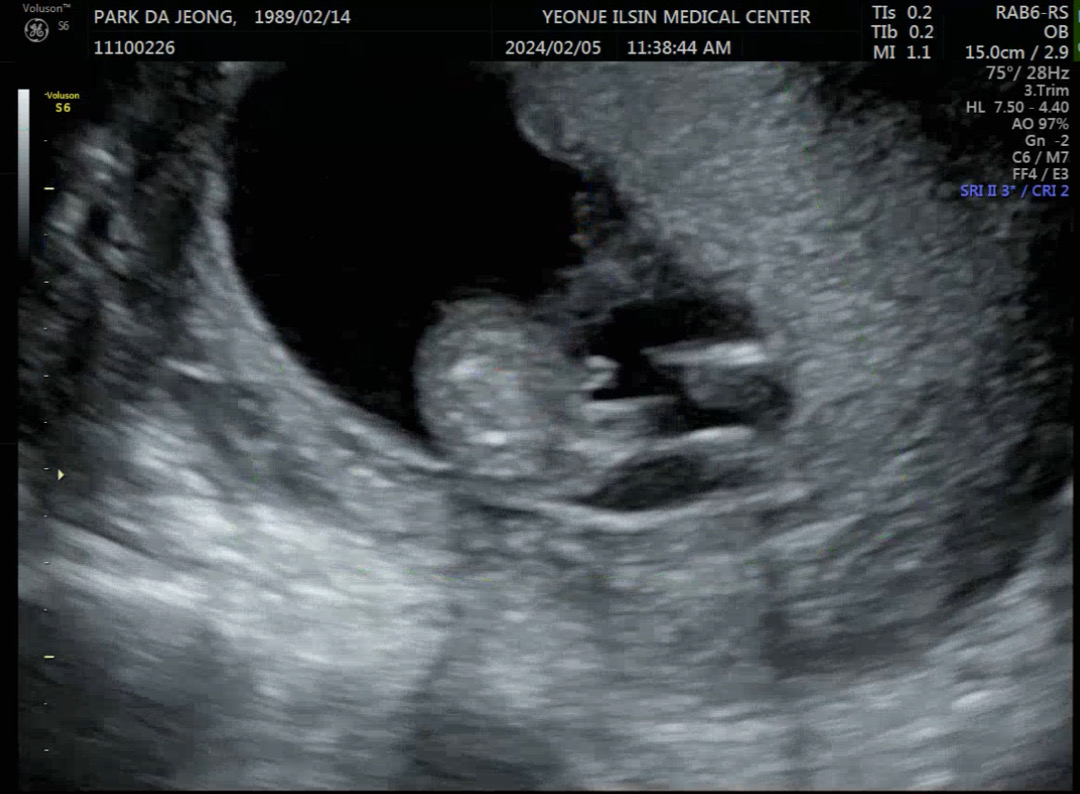

1차정밀때 아무것도없네요~ 하면서 딸인거같은 느낌으로 말씀주셨는데 2주뒤에 이거보면서 여기 있네요~~ 하고 너무 잘보이는데요 하면서 아들인듯 말씀해주셨어요!! 바뀔수도있을까요?? 딸이라고 철썩같이믿다가 아들이라니까 없던 딸을 잃은 기분이었는데 또 바뀌면 이번엔 아들잃은 기분일것같아요 ㅋㅋ

아들이네요 ㅎㅎㅎㅎ축하들려용

아들같아요 ㅎㅎㅎ